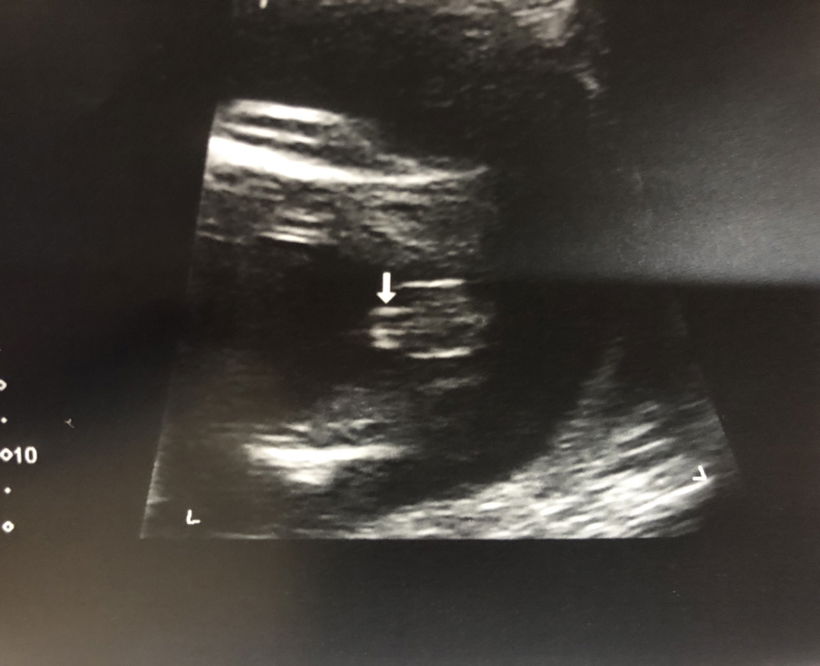

Had my detailed scan last friday. And I am expecting a boy. I have gotten a few scan pictures. And have been staring at this one for some time now 😂 Is this the scanning of something between the legs that indicate its a boy?

Yesss its a very clear potty shot! Congratulations!